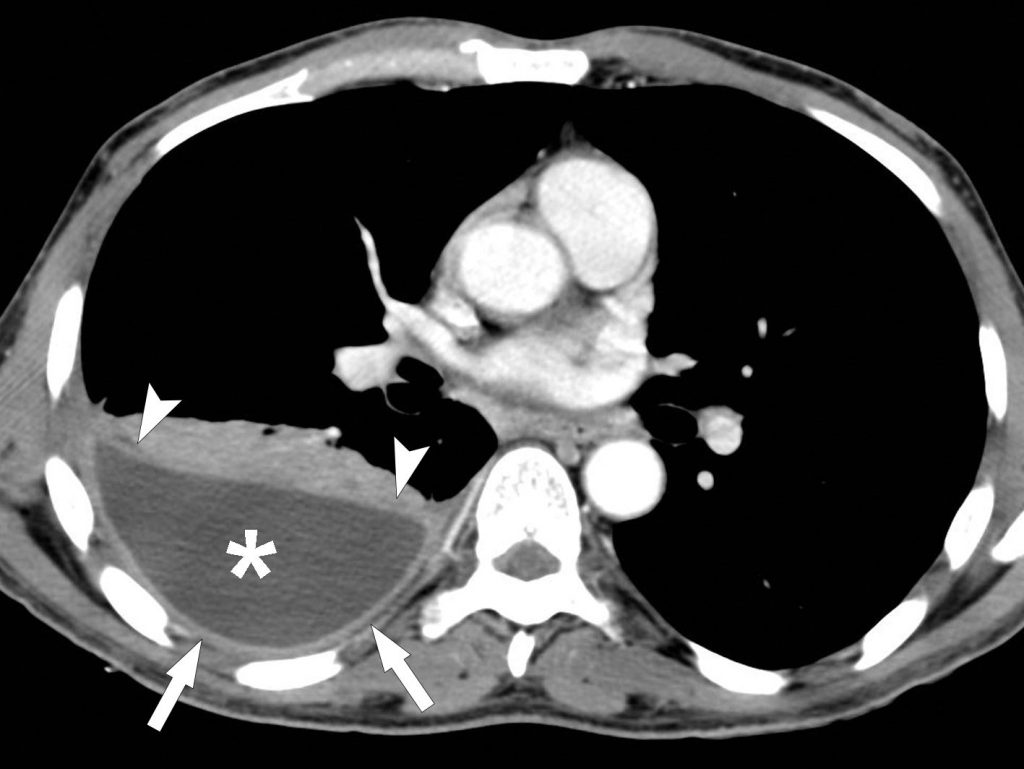

Fig. 91.5. Radiographie de face et scanner d’un épanchement pleural droit compressif.

L’hémithorax droit est entièrement opaque (astérisque en A) et la trachée est légèrement refoulée vers la gauche (flèches en A). Le scanner chez le même patient montre l’épanchement pleural droit de grande abondance (astérisque en B) refoulant le médiastin vers la gauche (flèches en B).

Source : CERF, CNEBMN, 2022.